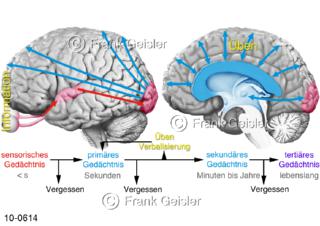

Bildergalerie Nervensystem

Bilder zum Nervensystem,dem Gehirn, Teil des zentralen Nervensystem, Zentralnervensystem ZNSmit Rückenmark, Abbildungen zum Nervengeflecht (Nervenplexus), die Verflechtungen von Nervenfasern, aus der Wirbelsäule hervortretende Nervenäst sowie Nervenzellen der Nerven